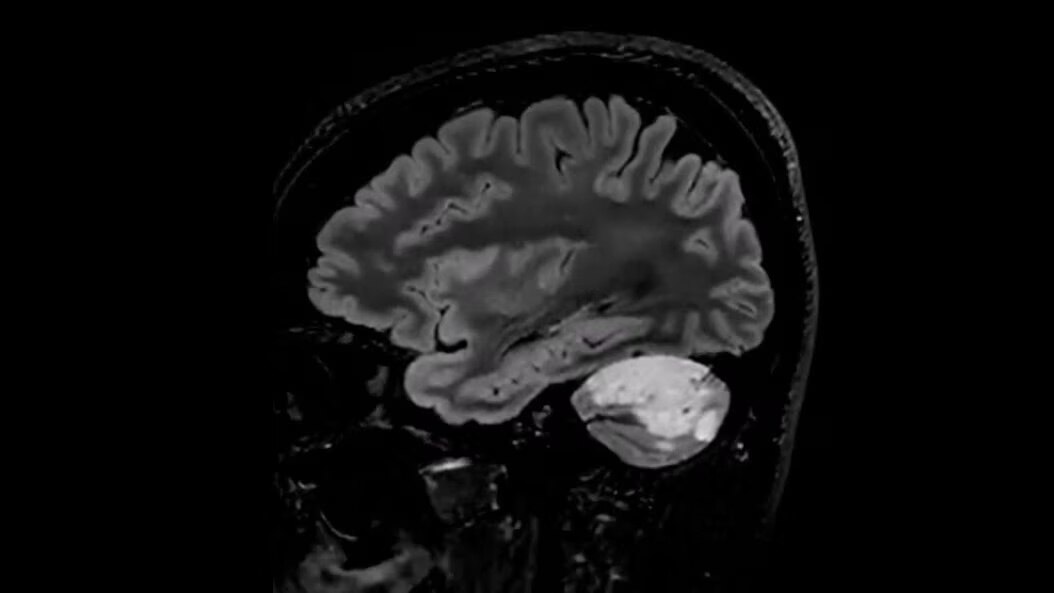

Neuro MRI for SIGNA

Explore Neuro MRI for SIGNA, a wide range of techniques for precise brain, spine and nerve anatomy to enhance treatment monitoring and neuro imaging efficiency, effortlessly.